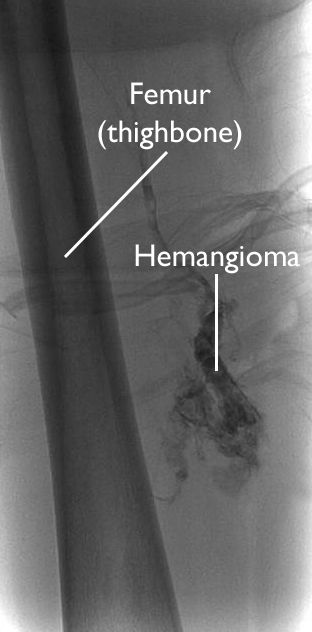

angiogram of hemangioma in thigh

This angiogram image shows a hemangioma deep in the thigh.

Angiogram. In this test, dye is injected into the surrounding blood stream making the hemangioma show up in an X-ray image.